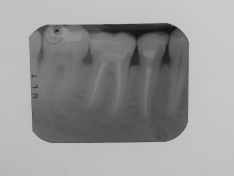

Fig 11 Controllo radiografico